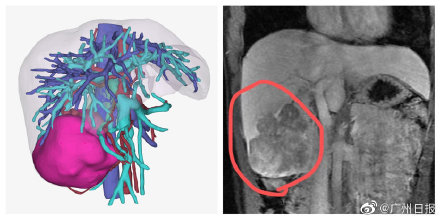

医生表示,“慢乙肝”患者本身具备肝癌高风险,加之小黎长期有不良作息和生活习惯,导致了这么严重的结果。幸好,小黎身体状况不错,肿瘤没有侵犯临近器官,也没有远处转移,医生最终为她做了右半肝切除手术,切除肿瘤,术后小黎恢复良好。(广州日报·新花城记者:轩慧)